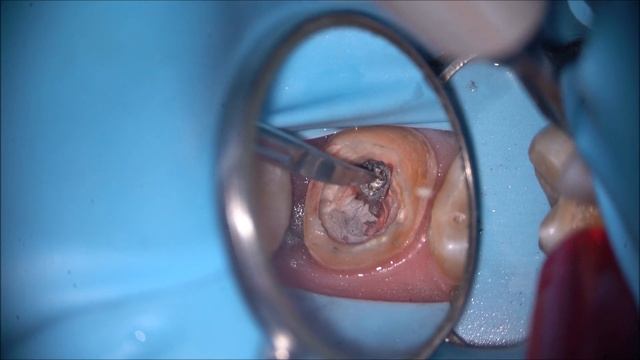

Извлечение культевой вкладки. смотреть онлайн

01:08

Извлечение культевой вкладки.

Как Сделать Красиво и Качественно 40 просмотров